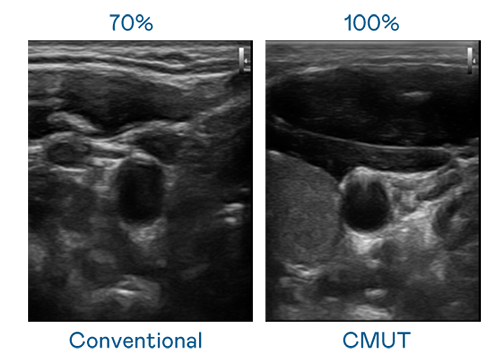

CMUT 技术是一种用电容式微机电元件来产生超音波讯号的技术。与传统 PZT 压电式技术相比,CMUT 频宽增加 30%,更宽频的超音波讯号让影像解析度大幅提升,是实现高影像品质医疗超音波扫描、促进精准医疗发展的关键技术。

超音波影像的解析度高低,首先取决于探头能发出的讯号频宽。巅峰国际 CMUT 可提供高清晰的超音波讯号,提供高频宽、高灵敏度、影像纹理细节更高的超音波影像,协助医护人员缩短影像判读时间及利用精准的医疗影像进行诊断。